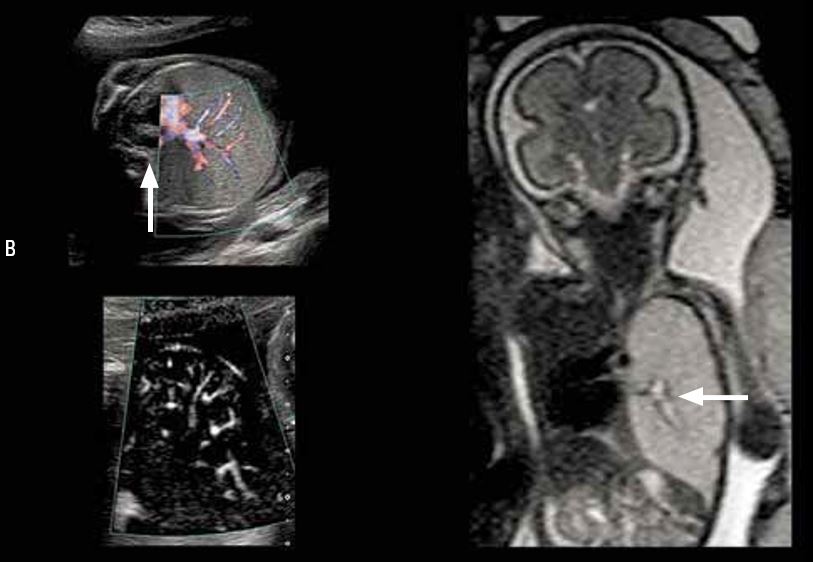

Патологічні зміни судин хоріального сплетення (мал. 5)

Папілома хоріального сплетення — це дуже рідкісна доброякісна пухлина, що добре кровопостачається, та становить менше 1 % пухлин головного мозку. Пік частоти захворювання спостерігається приблизно в 6 місяців.

Про гіперехогенне утворення свідчить вентрикуломегалія або гідроцефалія, що спостерігаються у внутрішньоутробний період.

При цьому в пухлині іноді виявляються мікрокальцифікати або крововилив. Застосування методу ультразвукової візуалізації не завжди можливо для диференціальної діагностики утворень цього виду та папілярної карциноми сплетення. Менінгіома — це пухлина, що дуже рідко зустрічається у дітей.

Мал. 5. Патологічна зміна судин хоріонічного сплетення, нерезектабельна:

A, B, C - пренатальне ультразвукове обстеження на 32-у тижні вагітності;

D — постнатальне черезтім’ячкове ультразвукове обстеження;

E – постнатальна МРТ; фронтальний зріз T1 після введення контрастної речовини;

гіперваскулярне утворення спричиняє синдром «обкрадання», ускладнений широкими ішемічними ураженнями паренхіми

Порівняння чутливості технології SMI із звичайним енергетичним допплерівським картуванням при візуалізації мікросудин.

При ультразвуковому дослідженні у пре- або постнатальний період візуалізація гіперваскулярного утворення, що спостерігається при МРТ із відстроченим контрастуванням після ін'єкції, можлива лише за допомогою технології SMI.

Емфізема легень (рис. 8)

При звичайному енергетичному допплерівському картуванні дослідження гемодинаміки нирок, печінки, стінки кишківника і паренхіми легень обмежене внаслідок малого розміру судин, розташованих дистальніше живлячих стовбурів. Тепер для ідентифікації периферичних судин з дуже малим діаметром можна використовувати режим SMI.

Візуалізація кровотоку у цих судинах значно спрощується завдяки тканинній субтракції зі збереженням чудової просторової роздільної здатності. Достовірна візуалізація мікросудин стає доступною для аномальних структур та судин мозку та плаценти. Дослідження судинної системи легень залежить від передлежання плода і обмежено кістковими структурами, що їх перекривають.

Мал. 8. Емфізема легень (надано лікарем Ш. Дюраном (Ch. Durand), Гренобль, Франція):

A - аксіальний зріз грудної клітини; ультразвукове допплерівське дослідження (метод ADF);

розтягнення паренхіми лівої легені; серце зміщене у правий геміторакс, стрілка (A);

при стандартному енергетичному доплерівському картуванні візуалізується лише проксимальна частина судинної системи;

B - Аксіальний зріз грудної клітини. Метод SMI. Виконується картування судин усієї паренхіми легень для візуалізації типу судинної мережі;

C - фронтальний зріз; МРТ-послідовність SSFSE T2; розтягнення паренхіми легені нижче за обструкцію бронха;

рідина на бронхограмі вище (стрілка)